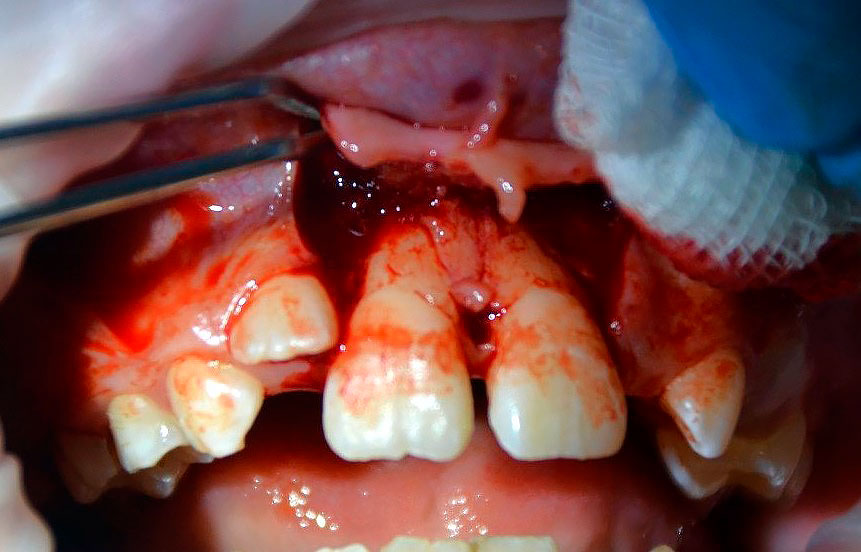

Распатором проведено аккуратное отслаивание слизисто-надкостничного лоскута, по возможности избегая касания корней зуба для максимального сохранения оставшихся периодонтальных волокон и клеток на поверхности корней зубов (Рисунок 10).

Рисунок 10. Отслоен слизисто-надкостничный лоскут. Признаки отсутствия костной ткани в апроксимальных участках и на вестибулярной поверхности корней зубов 1.1 и 2.1 на протяжении более чем 23 длины корней.

Визуализированы и удалены 2 эластических кольца из области апикальной трети зубов 1.1, 2.1 путем захвата кольца иглодержателем и рассечения ножницами, антисептическая обработка 0.05% раствором Хлоргексидина. Гнойного отделяемого не обнаружено, открытый кюретаж не проводился (Рисунки 11, 12).

Рисунок 11. Визуализированы и удалены два эластических кольца из апикальной трети пародонта зубов 1.1, 2.1.